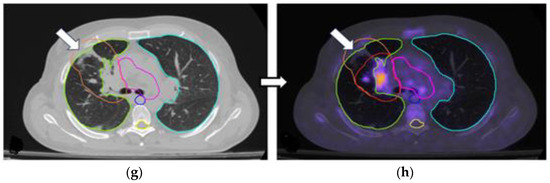

3.2. Changes in the Primary Tumor and Nodal Coverage